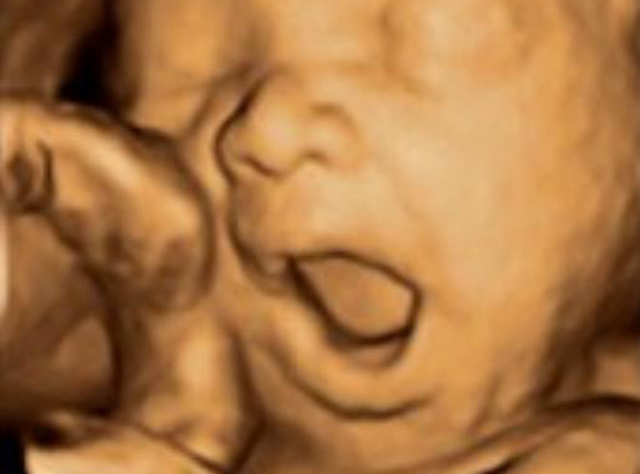

• 26 Semanas

26 Semanas

*Inicio del reflejo de protección ante sonidos inesperados y fuertes

*Traga 1/2 litro de líquido amniótico diario para mantener equilibrio hídrico del útero y ayuda a perfeccionar su sistema digestivo.

*Aparece reflejo de succión, empieza a chuparse los dedos.

*La preferencia de una mano en la boca puede indicar el uso de la preferencia una vez nazca.

*Los pulmones del feto aún no funcionan pero inician movimientos con el diafragma y pulmones como práctica de preparación al momento de nacer.